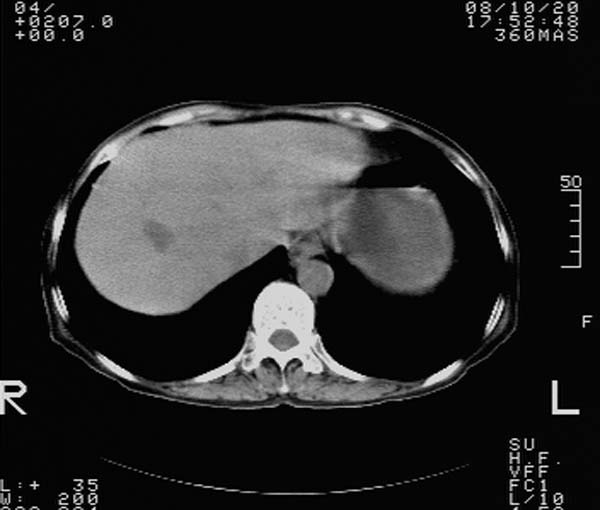

f,67y。反复右上腹痛。余无异常。

前五幅未服造影剂。后面图像有上传重复的。请战友们发表意见。

胆囊结石、胆囊癌伴邻近脏器受侵,不除外黄色肉芽肿性胆囊炎,建议增强扫描。肝多发囊性占位性病变,囊肿或囊性转移。

胆囊内结石,胆囊壁不规则增厚,胆囊胃窦区解剖结构欠清晰,楼主提示为少见病,考虑bouveret综合征?黄色肉芽肿性胆囊炎?肝内多发低密度占位,建议增强或b超